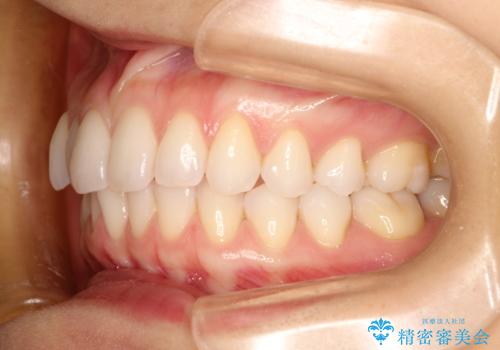

- インビザライン

- 1年6ヶ月

- 10-30回

また、ホワイトニングも一緒にご希望されたため、挙式のタイミングに合わせてレーザーホワイトニングを施術させていただきました。